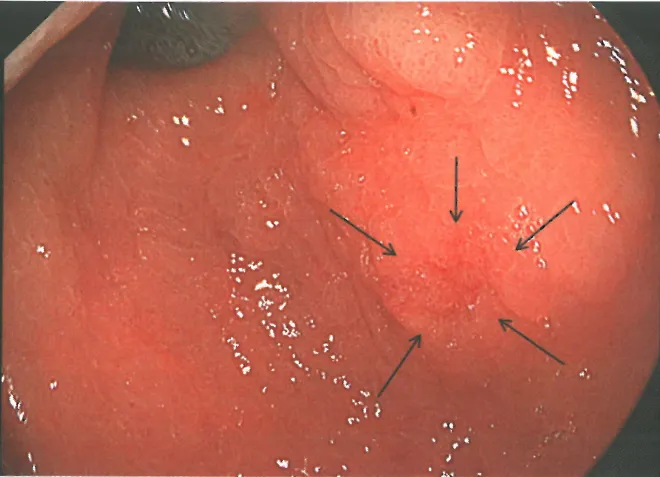

• 内镜下表现为平坦、凹陷或隆起(息肉样)的病变,伴糜烂/溃疡及色泽改变(红斑样

• 窄带成像放大内镜可显著提高内镜评估准确性,可关注表面上皮结构和上皮下血管

表现为平坦、凹陷或隆起(息肉样)的病变